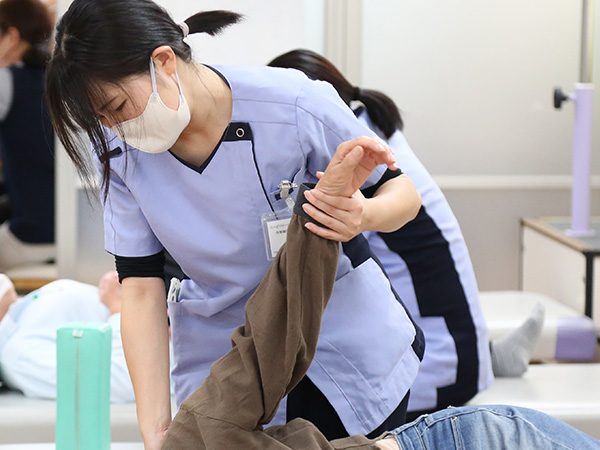

REHABILITATIONリハビリテーション科

患者様一人ひとりの症状に合わせたリハビリを提供させて頂いております。

予約制ではありませんので、症状や都合にあわせて通院して頂いています。

毎日通われる方、また仕事の休みに合わせて、週に一度通われる方など通院の仕方も様々ですが、お待たせしないよう、理学療法士、作業療法士の他、あんまマッサージ師も数名在籍しており幅広い対応がすぐにできるようになっています。

❶ロコモティブシンドロームを防ぐための積極的なリハビリ

当クリニックでは、ロコモ予防に力を入れており、特に発症リスクが高い高齢の方を対象に、早期治療による痛みの軽減、その後の運動機能の低下を防ぐリハビリテーションを積極的に提供しています。経験豊富な理学療法士が、一人ひとりの状態に合わせた適切なプログラムでサポートいたします。

❷スポーツによるケガや障害に対し、積極的にリハビリ

骨折や肉離れなどの治療後に、低下した運動機能の回復を目的としたリハビリテーションを行います。またそれに加え、再発予防を目的としたケアも行っています。日本整形外科学会認定スポーツ医の院長と経験豊富な理学療法士が、一人ひとりの状態に合わせた適切なサポートをいたします。